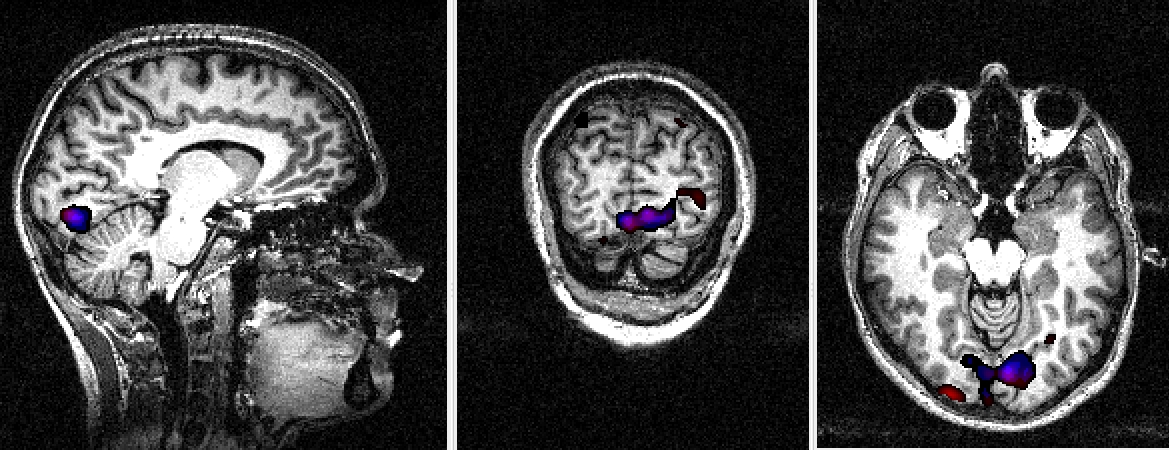

Retinotopic mapping of human visual cortex using fMRI is a well established method (Sereno et al. (1995); Warnking et al. (2002)) that allows to properly delineate low visual areas. It uses four separate experiments with 4 periodic stimuli (an expanding/contracting ring and a rotating counter or anti-counter clockwise wedge) to measure respectively eccentricity and polar angle maps. For this study, we only used functional MRI data corresponding to the expanding ring experiment (240 volumes acquired each 2 seconds). The periodic visual stimulus expanded from 0.2 to 3 degrees in the visual field during 32 seconds and was repeated fifteen times. This periodic stimulation generated a wave of activation in the retinotopic visual areas (Engel et al. (1994)), located in the occipital lobe, at the frequency of 1/32 Hz measured at a discrete temporal sampling of 2 seconds (equivalent to 1/16 temporal bins). After IC analysis of these functional data, using our R function \codef.icast.fmri.gui(), 18 and 15 components were automatically extracted respectively with tICA and sICA. In this experiment, we searched for components corresponding to cortical activation at the frequency of the visual stimulation. tICA and sICA extracted more (noisy) components than the ones specific to the stimulus. Indeed, the main problem with fMRI data is that each activated voxel of each volume contains a mixture of the signal of interest (BOLD effect) with several confound signals with several origins: ocular movement, heart rate, respiratory cycle, or head movement. Figure 10 shows the temporal and spatial components at the frequency of the visual stimulation corresponding to the cortical activation of interest. The computed phases are (approximatively) respectively equal to , and for tICA (green, red and blue components) and and for sICA (green and red components). Figure 10 displays on the corresponding anatomical image the cortical localization of these extracted components. For tICA and for each temporal component, this is done by selecting in the associated column of the estimated mixing matrix (see equation (4)) the most active voxels, defined arbitrarily (see Beckmann and Smith (2004) for another approach) as those whith a value above the 95% quantile (in absolute value). For sICA, we also thresholded arbitrarily each component at the 95% quantile. Based on the retinotopy property of the visual system, the expanding ring generates a cortical activation wave moving from the posterior part to the anterior part of the occipital lobe. As indicated in Figure 10 the computed phases of the extracted components increase as expected from the posterior to the anterior part of the occipital lobe.

![]() |

||

|||

Experiment 2 : Color center mapping

In this experiment, we presented to the subject two stimuli, a set of chromatic rectangles (Mondrian like patterns) and the same patterns in an achromatic version (Figure 11). Each chromatic and achromatic sets of rectangles were periodically presented during successive blocks of 10 seconds. Our analysis was made on 120 functional volumes acquired each 2 seconds. Because we were only interested in visual areas, we used a mask to select only the occipital part of each volume. Using our R function \codef.icast.fmri.gui(), 21 and 20 components were automatically extracted with tICA and sICA respectively. As shown in Figure 11, we found both with tICA and sICA one periodic component at the frequency of the stimulus.

As shown in Figure 12, the voxels containing the components extracted using temporal and spatial ICA were localized as expected in the same ventral cortical region, called V4-V8, known to be sensitive to color perception (Wade et al. (2002)).